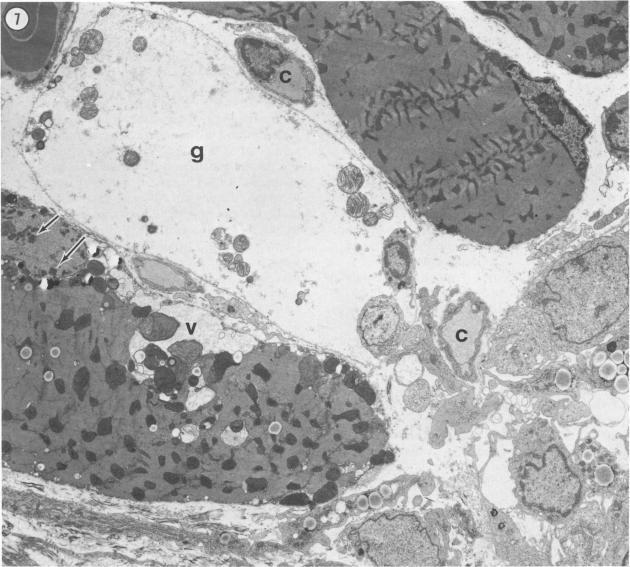

In this study, the authors examined the effect of the anti-tumor agent Adriamycin, a known cardiotoxin, on mouse heart, diaphragm, and gastrocnemius muscle. Using an established model of Adriamycin cardiac toxicity, they found that 4 days after the intraperitoneal injection of 20 mg/kg of Adriamycin, characteristic heart lesions, including vacuolation of the sarcoplasmic reticulum, interstitial edema, and mitochondrial degeneration, were demonstrated in all treated animals. Furthermore, similar, but much more severe, myocyte damage was demonstrated in the diaphragm; muscle toxicity followed a decreasing gradient of injury from the peritoneal to the thoracic surface of the tissue. On the other hand, treatment with Adriamycin resulted in an increase in the size and number of lipid droplets in the red fibers of the gastrocnemius muscle without any other ultrastructural evidence of drug-induced damage to myocytes. An examination of the pharmacokinetics and metabolism of Adriamycin after intraperitoneal treatment revealed that relative drug levels in muscle (diaphragm much greater than heart much greater than gastrocnemius) paralleled the degree of ultrastructural damage observed. This study indicates that treatment with Adriamycin can produce significant injury to non-cardiac muscle in a fashion that strongly resembles the characteristic pattern of Adriamycin-related damage to the heart, and that the degree of myocyte damage is apparently dependent upon the Adriamycin concentration in the tissue.

在本研究中,作者研究了抗肿瘤药物阿霉素(一种已知的心脏毒素)对小鼠心脏、膈肌和腓肠肌的影响。他们使用已建立的阿霉素心脏毒性模型,发现腹腔注射20mg/kg阿霉素4天后,所有接受治疗的动物均出现了特征性的心脏病变,包括肌浆网空泡化、间质水肿和线粒体变性。此外,在膈肌中也发现了类似但更为严重的心肌细胞损伤;肌肉毒性从组织的腹膜面向胸表面呈现递减的损伤梯度。另一方面,阿霉素治疗导致腓肠肌红色纤维中脂滴的大小和数量增加,而没有任何其他药物诱导的心肌细胞损伤的超微结构证据。对腹腔注射阿霉素后的药代动力学和代谢进行检查发现,肌肉中的相对药物水平(膈肌远高于心脏,心脏远高于腓肠肌)与观察到的超微结构损伤程度平行。这项研究表明,阿霉素治疗可对非心肌产生显著损伤,其方式与阿霉素相关的心脏损伤特征模式极为相似,并且心肌细胞损伤程度显然取决于组织中阿霉素的浓度。